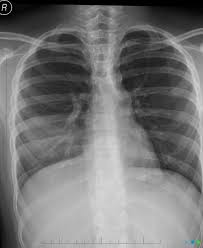

Mucus also known as phlegm when it s produced by your respiratory system lines the tissues of your body such as your nose mouth throat and lungs and it helps protect you from infection. Mucus plug the excessive secretion of slippery substance produced by the cells lining the airways of the lungs is a result of various respiratory conditions that exhibit mucus hypersecretion. Mucus is a normal slippery and stringy fluid substance produced by many lining tissues in the body. They work by breaking the chemical bonds in mucus to help make the secretions easier to cough up.

Mucus a slippery and sticky fluid found throughout the body plays an important role in the health of the respiratory system. If the mucous plug is in one of the smaller bronchial tubes the air behind the plug and the smallest airways called alveoli gets absorbed and this condition is called atelectasis. Mucus also acts as a trap for irritants like dust smoke or bacteria. Mucus plugs in the lungs generally develop in response to chronic underlying conditions of the respiratory or nervous system that weaken the lungs or surrounding muscles.